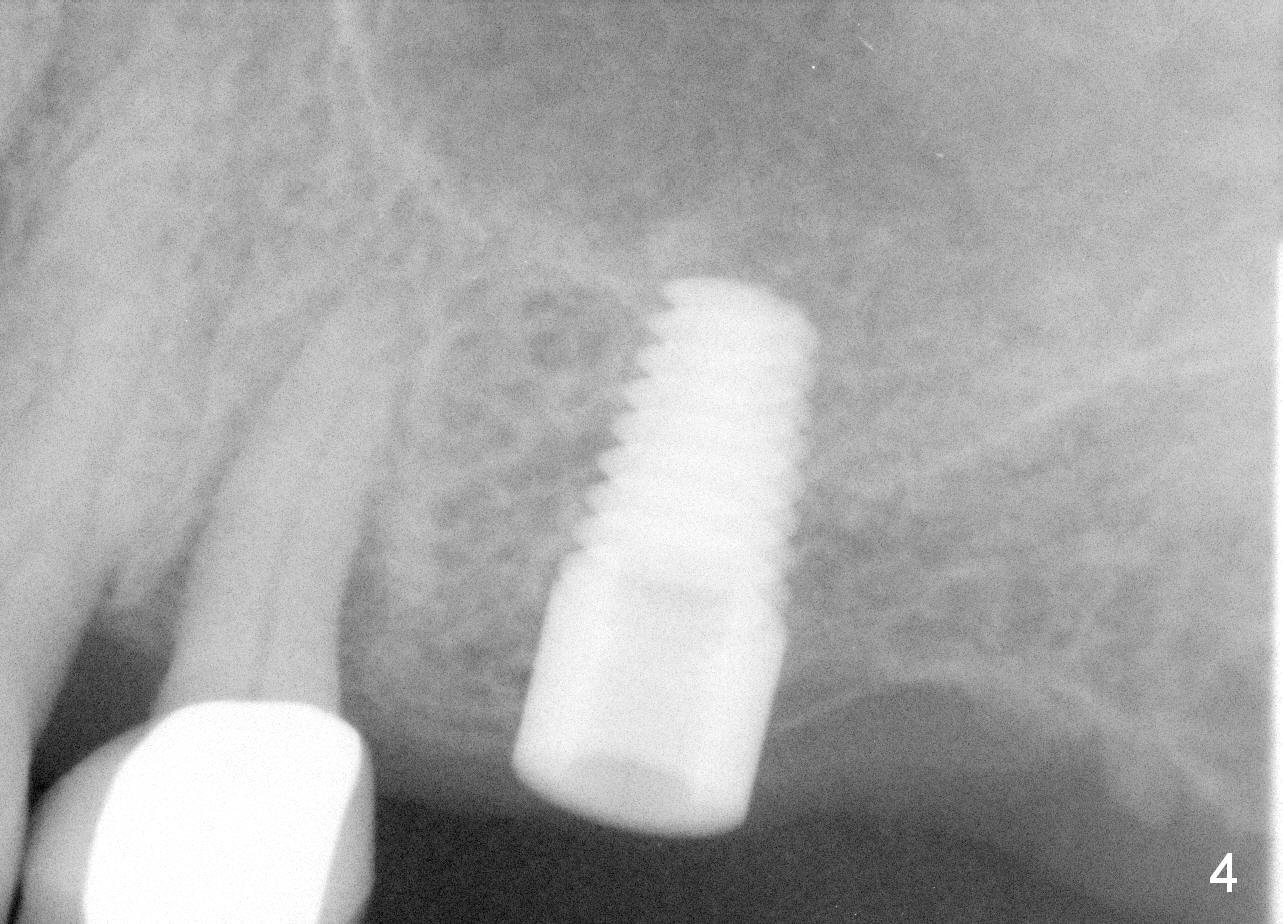

Mrs. Goh (71 years old) has lost 4 upper molars (Fig.1,6). The 1st sign of overload is increased periodontal space around the tooth #13 (Fig.1 *). The best way to tackle the overload is to place 4 implants. The 1st step is for the site of #14 (Fig.2: design; Fig.3: 4.5x11 mm tap; Fig.4: 5x11 mm implant). The 2nd sign of overload is repeated dislodgement of the implant supported crown. The 3rd sign of overload is bone loss around the implant 6 months post cementation (Fig.5 *). The 4th sign of overload is subgingival crown fracture of the tooth #5 (Fig.6).